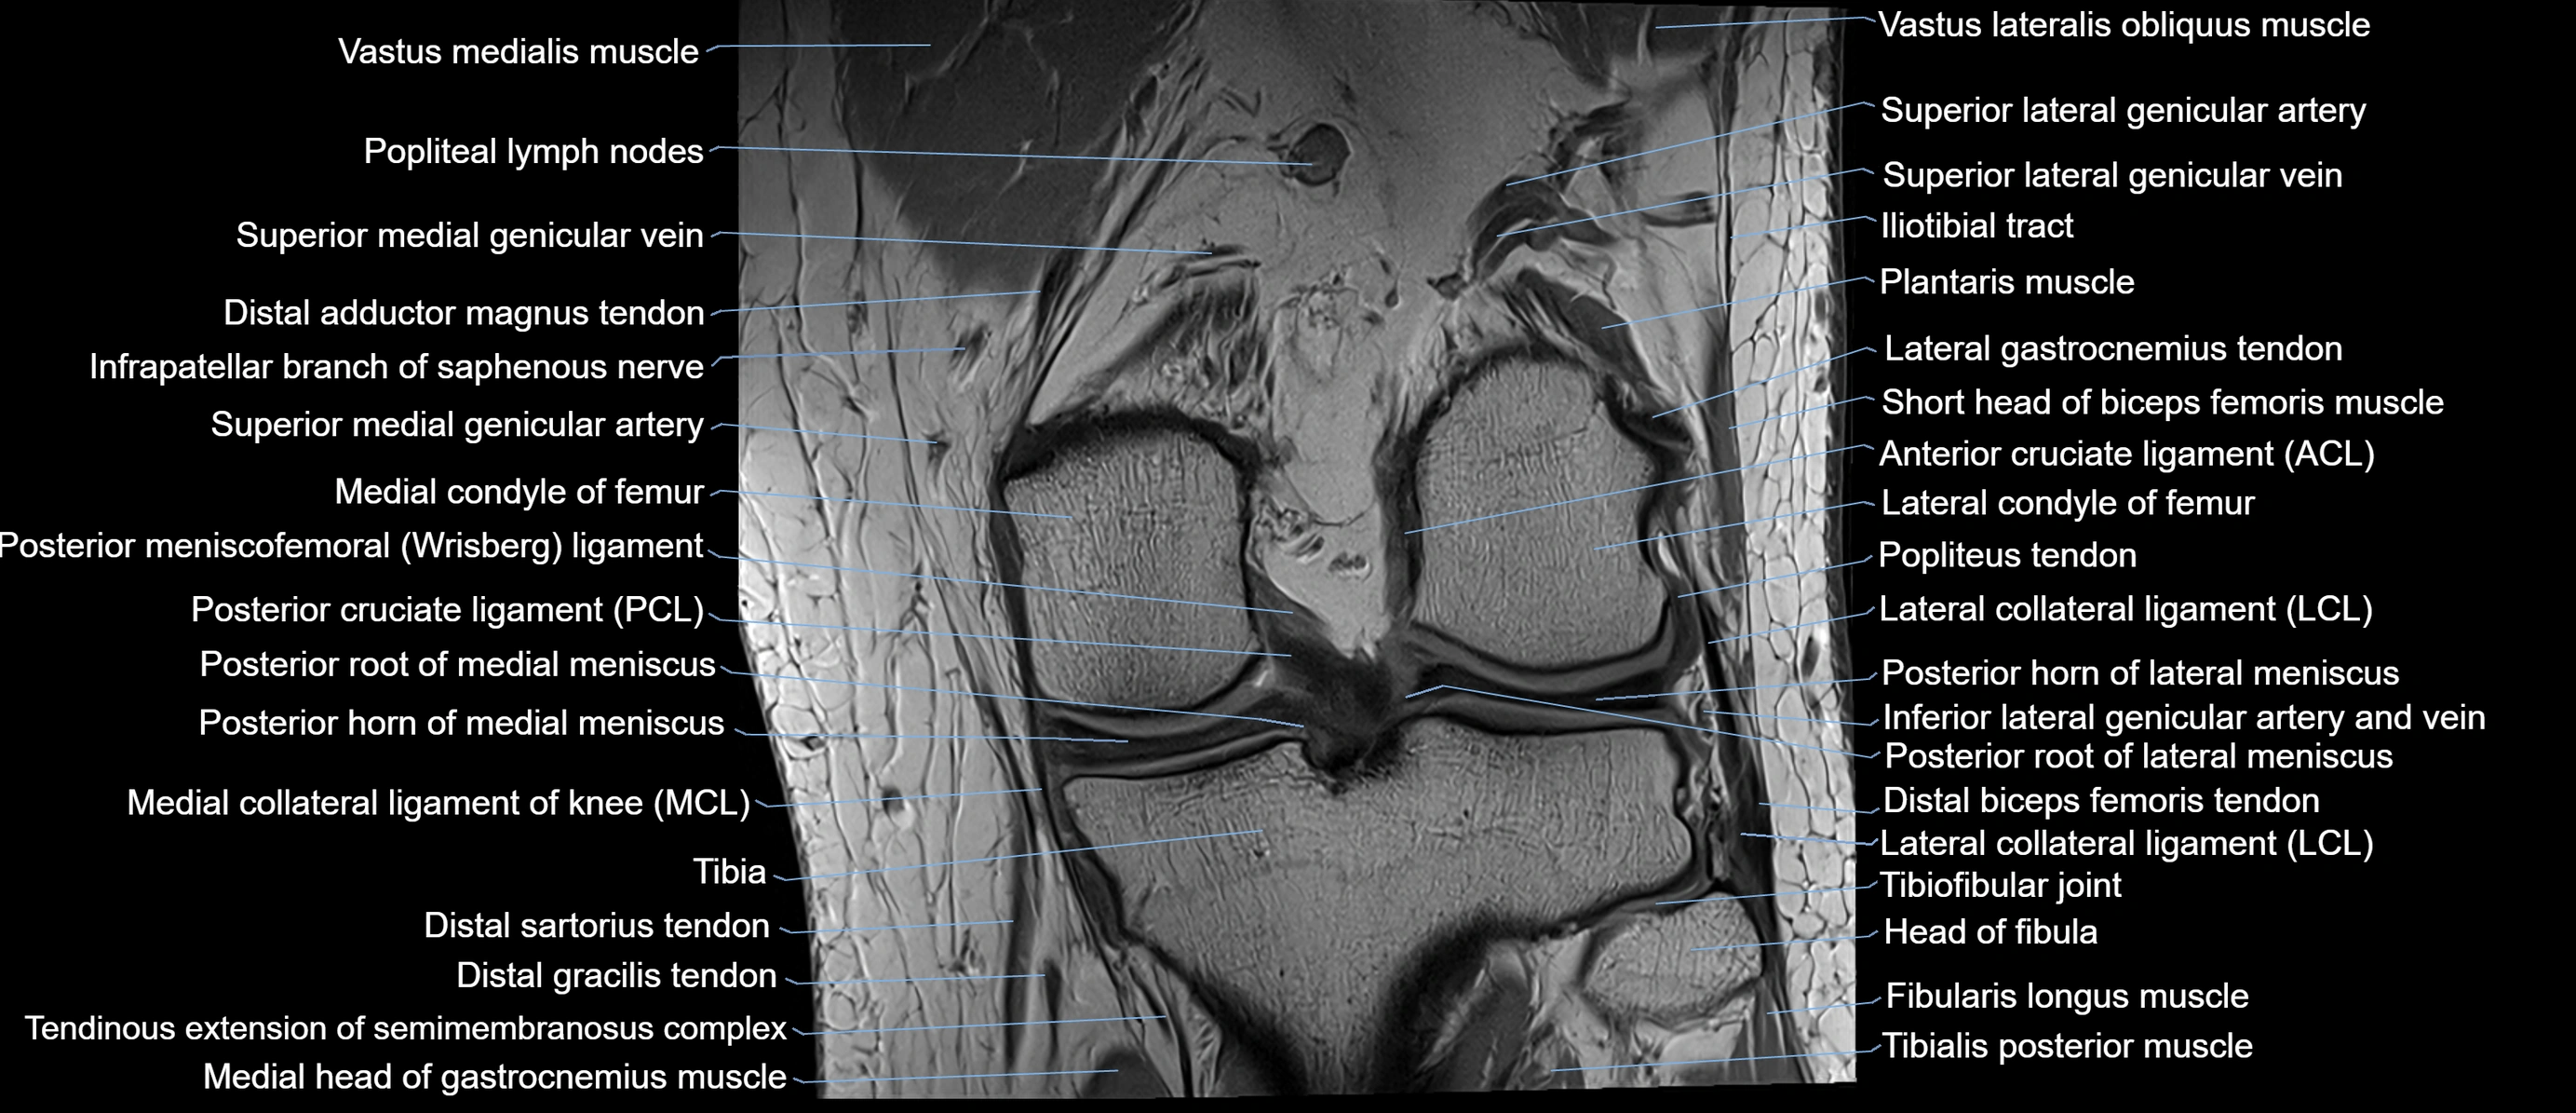

- Anterior cruciate ligament

- Lateral collateral ligament

- Lateral condyle of femur

- Lateral condyle of tibia

- Medial collateral ligament

- Medial condyle of femur

- Medial condyle of tibia

- Medial head of gastrocnemius muscle

- Medial meniscus

- Oblique popliteal ligament

- Plantaris muscle

- Popliteal lymph nodes

- Popliteal vein

- Popliteus tendon

- Posterior cruciate ligament

- Posterior horn of lateral meniscus

- Posterior horn of medial meniscus

- Posterior root of lateral meniscus

- Posterior root of medial meniscus

- Superior lateral genicular artery

- Superior lateral genicular vein

- Superior medial genicular artery

- Superior medial genicular vein

- Superior tibiofibular joint

- Tibia

- Vastus Lateralis Obliquus Muscle

- Vastus lateralis muscle

- Vastus medialis muscle